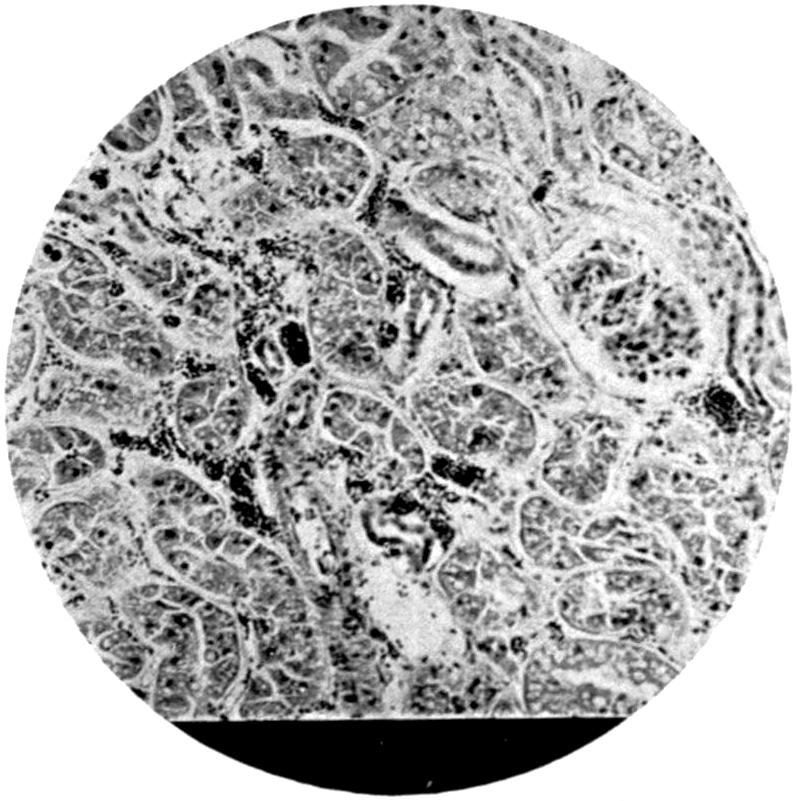

Plate I. 92

Plate II. 93

Plate III. 95

Plate IV. 276